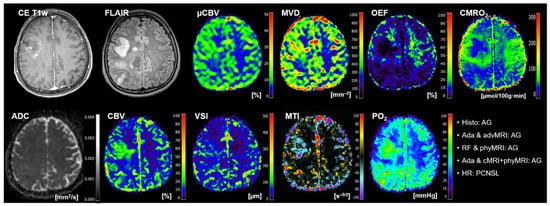

- The conventional anatomical MRI (cMRI) protocol for clinical routine diagnosis of brain tumors included, among others, an axial fluid-attenuated inversion recovery (FLAIR) sequence as well as a high-resolution contrast-enhanced T1-weighted (CE T1w) sequence.

- The advanced MRI (advMRI) protocol for clinical routine diagnosis of brain tumors was extended by axial diffusion-weighted imaging (DWI; b values 0 and 1000 s/mm2) sequence and a gradient echo dynamic susceptibility contrast (GE-DSC) perfusion MRI sequence, which was performed using 60 dynamic measurements during administration of 0.1 mmol/kg-bodyweight gadoterate-meglumine (Dotarem, Guerbet, Aulnay-Sous-Bois, France).

- The physiological MRI (phyMRI) protocol included the innovative MRI techniques of vascular architecture mapping (VAM) [31] for the assessment of microvascular architecture and neovascularization activity, as well as the quantitative blood-oxygenation-level-dependent (qBOLD) imaging approach [19,32] for assessment of tissue oxygen metabolism and tension. The VAM approach [33,34] additionally required a spin-echo DSC (SE-DSC) perfusion MRI sequence conducted with the same parameters and contrast agent injection protocol as described for the routine GE-DSC perfusion MRI. Details of our strategy to minimize adverse effects due to differences in time to first-pass peak and contrast-agent leakage, which could significantly affect the data evaluation, were previously described [33,34]. The qBOLD approach [19,32] additionally required a multi-echo GE sequence and a multi-echo SE sequence for the mapping of the transverse relaxation rates R2* (=1/T2*) and R2 (=1/T2), respectively. All phyMRI sequences for VAM and qBOLD were carried out with identical geometric parameters (voxel size, number of slices, etc.) and slice position as used for the routine GE-DSC perfusion sequence. The phyMRI protocol required seven minutes of extra scan time in total.